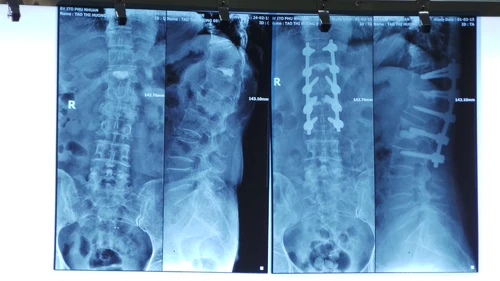

Ảnh chụp X-quang cho thấy

Ảnh chụp X-quang của ca bệnh hiếm gặp

Ngày 4-3, Bệnh viện Chấn thương Chỉnh hình Sài Gòn - ITO cho biết nơi đây vừa phẫu thuật thành công hai ca bệnh hiếm gặp do bất thường về cấu trúc giải phẫu ở đường thở. Đó là bà T.T.H (69 tuổi, Việt kiều Mỹ) bị gãy cột sống và ông T.N.D (47 tuổi, ngụ Hà Nội) bị hoại tử chỏm xương đùi, viêm dính đa khớp.

Cách đây 10 năm, bà H. bị trượt chân gãy cột sống. Tại Mỹ, trong quá trình gây mê chuẩn bị phẫu thuật, các bác sĩ phát hiện bệnh nhân không mở miệng được (cứng hàm) không thể đặt được nội khí quản nên ca mổ hoãn ngay lập tức. Bệnh nhân chỉ được bơm xi măng y khoa để cố định tổn thương cột sống. Qua lần phẫu thuật đó, bệnh nhân được gửi thư cảnh báo những khó khăn của mình khi phẫu thuật về sau.

Khi Việt Nam ăn Tết, trong lúc khom người kéo thùng đá lạnh, bà H. không may gãy cột sống lần 2. Tại ITO, các bác sĩ gặp nhiều khó khăn trong việc đặt nội khí quản để phẫu thuật, như đặt đèn soi vào thanh quản nhưng không thấy được nắp thanh quản, dây thanh quản…, các bác sĩ buộc phải đặt ống thở trong lúc bệnh nhân còn tỉnh. Đây là một quyết định táo bạo vì lâu nay các bác sĩ chưa thực hiện đặt mò ống đường thở như thế này. Sau khi đặt ống thành công, bệnh nhân được phẫu thuật cố định tổn thương cột sống thành công sau 3 giờ 30 phút.

Đối với bệnh nhân D. bị hoại tử chỏm xương đùi hai bên, cong lưng, cứng hàm, cứng cổ do viêm dính các đốt sống cổ, buộc phải thay khớp háng nhưng cũng gặp khó khăn trong việc đặt nội khí quản để phẫu thuật. Các bác sĩ cũng đặt nội khí quản bằng ống thông dẻo này đồng thời phẫu thuật thành công thay hai khớp háng cho bệnh nhân sau 2 giờ 30 phút.